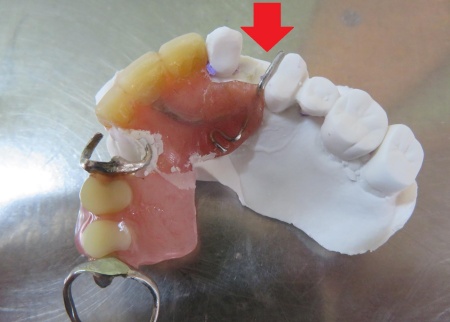

まず、現在使用している入れ歯をお口に装着した状態で、歯や顎の形を型取り材で写し取る印象採得を行います。

その後、出来上がった型をもとに石こう模型を製作しました。

次に、模型上で人工歯を追加する処置を行います。

折れた部分に合う人工歯を慎重に選び、入れ歯に丁寧に取り付けました。

治療中画像 治療中画像 治療中画像 治療中画像